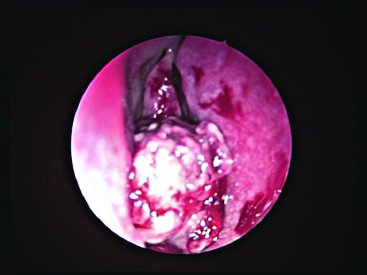

A 28-year-old female reported to the ENT outpatient department of our institution with the chief complaints of epistaxis and nasal obstruction in the right nasal cavity for the past 3 years and 6 months respectively. The frequency of episodes of epistaxis, though in form of mild spotting had increased to 6 episodes in the last one year. On examination a pinkish lesion was seen in the right nasal cavity [Table/Fig-1]. On probe test: the lesion was seen arising from the right inferior turbinate and was non tender but bled on touch. Clinically Nasal Polyp (including fungal), Papilloma, Haemangioma and Malignancy were kept as differentials for the said lesion. A Contrast Enhancement Computed Tomography Scan of the nose and paranasal sinuses was done which showed a 2.5 X 2.1 X 2.6 cm size enhancing lesion in the right nasal cavity, arising from the inferior turbinate with no bony erosion [Table/Fig-2]. As the lesion was small in size and at an accessible location, complete endoscopic excision was done. Mild postoperative bleeding was observed which was controlled by electrocautery. It would also be important to note that as our patient’s background features were not compatible with angiofibroma, she was not referred for angiography or embolization prior to surgery.

Ulceroproliferative lesion originating from right inferior turbinate.